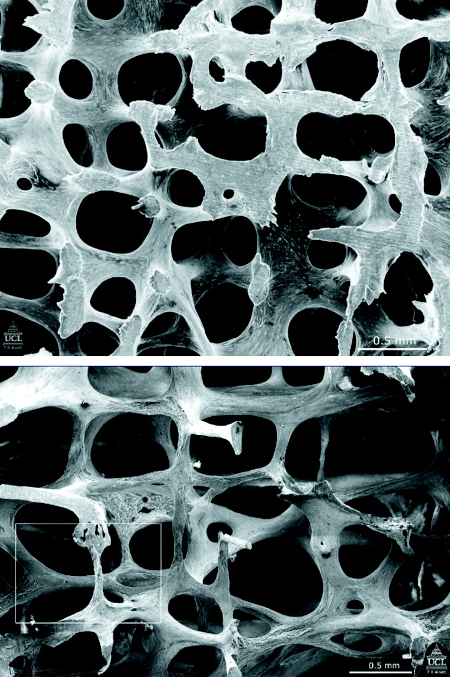

[Figure caption and citation for the preceding image starts]: Eletromicrografia de varredura que mostra a estrutura da vértebra L3 em uma mulher de 31 anos (parte superior) e em uma mulher de 70 anos (parte inferior). Observe que muitas das estruturas tipo placa se converteram em bacilos finosPoole KES, et al. BMJ 2006; 333: 1251; usado com permissão [Citation ends].

A massa óssea reduzida pode ser o resultado de um baixo pico de massa óssea ou a perda de massa óssea com o envelhecimento. A fragilidade dos ossos não é totalmente explicada por baixa massa óssea ou densidade óssea (massa/volume). A qualidade da microarquitetura óssea também contribui para a resistência óssea. A remodelação óssea e a mineralização constituem determinantes importantes da qualidade da microarquitetura óssea.